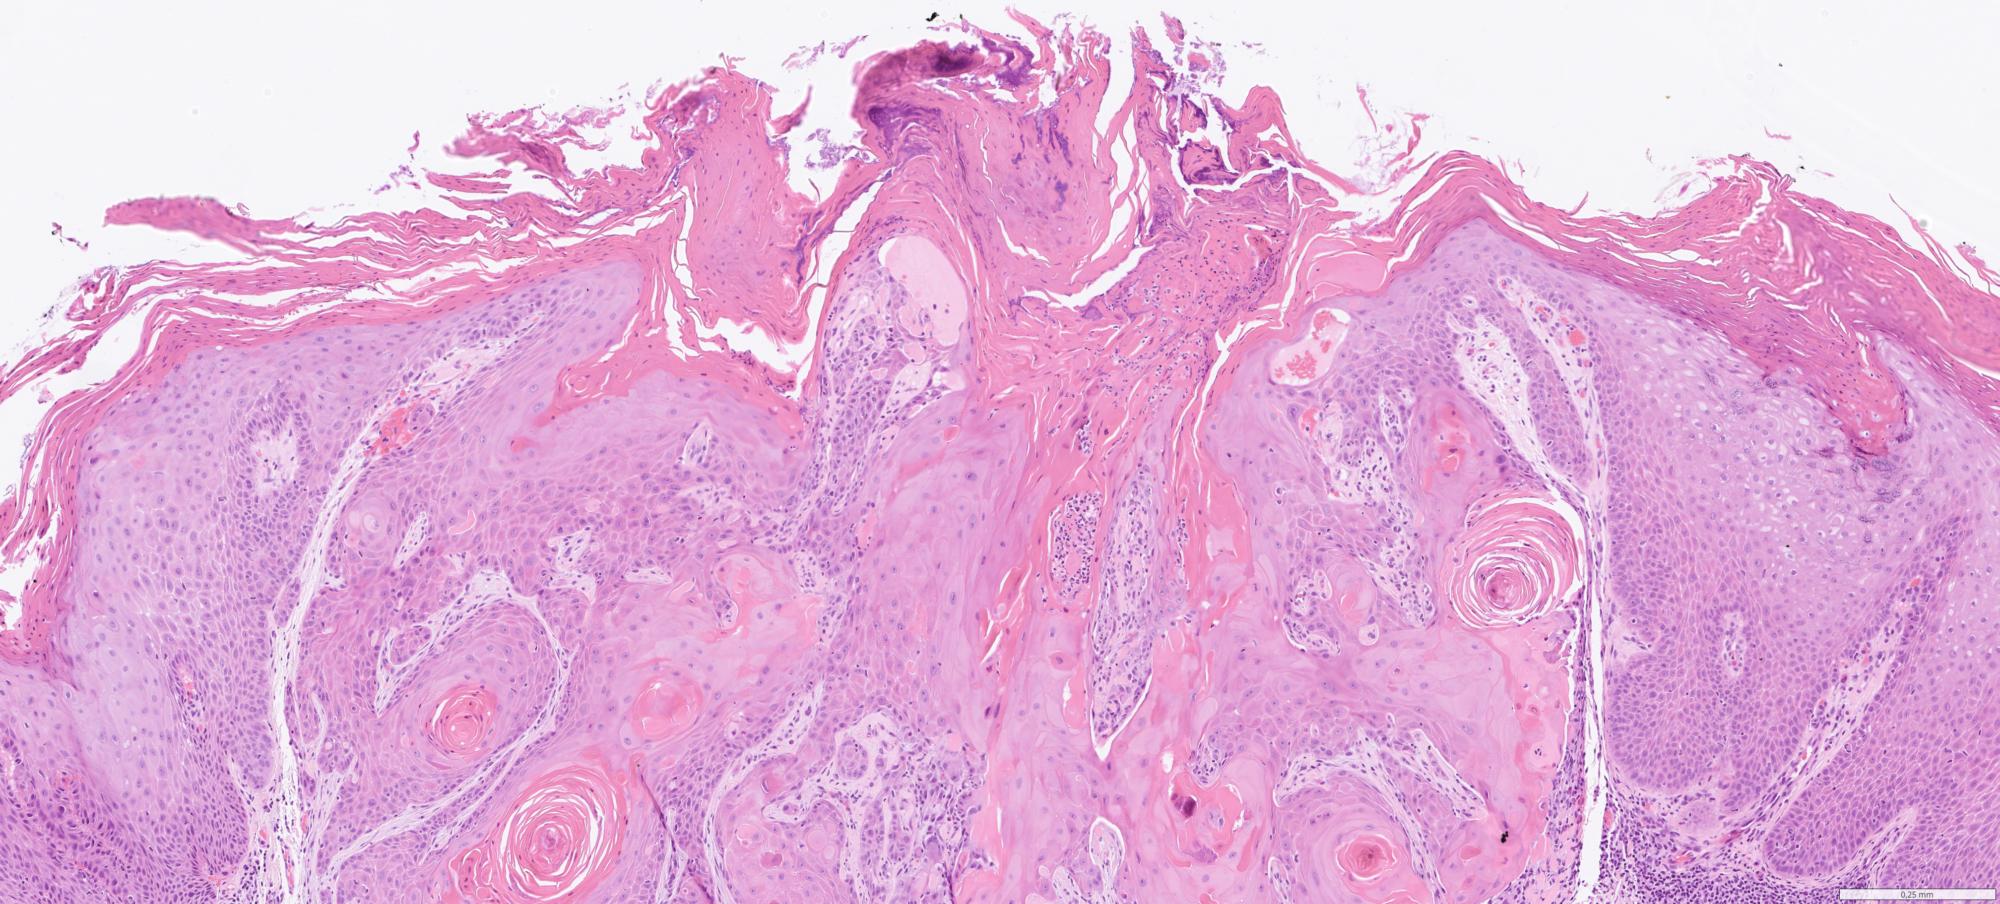

Whole slide pathology images from excision specimens of skin lesions diagnosed at the Department of Pathology at Clinical Department of Pathology at Linkopings University hospital. The dataset contains over 6000 WSIs from from xx excised and punsch biopsies representing a varity of diagnosis categoriesed as malignant melanoma, basal cell carcinom, squamous cell carcinoma and benign diagnosis (eg including melanocytic nevus).

Histopathology

malignant melanoma

basal cell carcinom

squamous cell carcinoma

benign